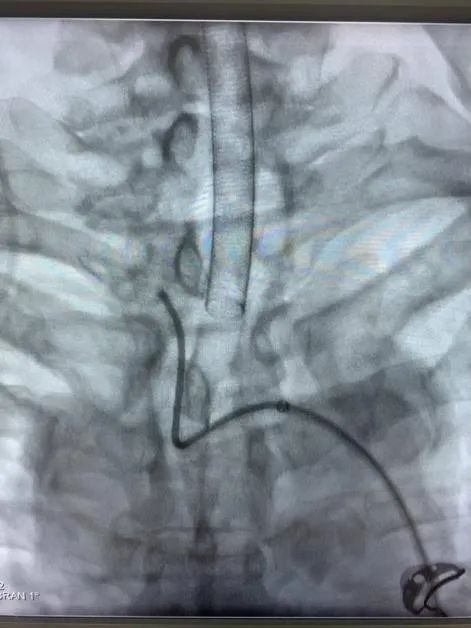

近日,省人民醫(yī)院神經(jīng)外科為一位高齡動脈瘤患者施行了介入治療,成功栓塞了破裂的大腦中動脈瘤?;颊咭蛲话l(fā)暈厥后頭痛不適入院,急診行顱腦CT檢查提示蛛網(wǎng)膜下腔出血,行顱腦CTA檢查后證實患者存在右側(cè)大腦中動脈瘤?;颊吒啐g,既往基礎(chǔ)病多,高血壓病、糖尿病、冠心病、雙側(cè)頸動脈硬化、雙側(cè)腹股溝疝術(shù)后等,手術(shù)風(fēng)險較大,經(jīng)家屬簽字同意后,當(dāng)日急診全麻下行“右側(cè)大腦中動脈瘤介入栓塞術(shù)”,術(shù)中見血管迂曲明顯,導(dǎo)管到位艱難,經(jīng)過努力,手術(shù)順利結(jié)束。術(shù)后予多次腰椎穿刺術(shù)釋放血性腦脊液,患者頭痛頭暈癥狀漸緩解?;颊咦≡褐委?/span>10天后順利康復(fù)出院,未留后遺癥。

動脈瘤主要有兩種治療方式:開顱手術(shù)和介入栓塞。兩種方法比較,介入栓塞手術(shù)時間短、康復(fù)快、不需開顱、可同時治療多個動脈瘤,適合高齡、分級高的患者,其中血管內(nèi)彈簧圈栓塞術(shù)是顱內(nèi)動脈瘤最常見的一種介入治療方式,隨著介入新材料、技術(shù)的不斷進(jìn)步,介入栓塞的優(yōu)勢日漸明顯。